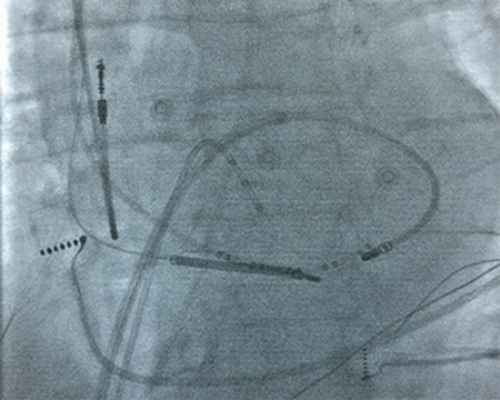

Под местной анестезией раствором новокаина 0,5% - 40,0 мл, пунктирована правая бедренная артерия с использованием интродьюсера SJM 7Fr Fast-Cath, через который проведен управляемый картирующий электрод Medtronic Marinr 7 Fr MC в полость левого желудочка. Проведено тщательное активационное картирование межжелудочковой перегородки на пароксизме тахикардии относительно начала QRS комплекса. Ранняя точка опережающая QRS комплекс на 28 мсек, обнаружена в задненижних отделах межжелудочковой перегородки.

Рисунок 3. Правая косая проекция. Рентгенограмма, иллюстрирующая расположение аблационного электрода в левом желудочке. Аблационный электрод (ABL) позиционирован в задненижнем отделе МЖП. Диагностический четырехполюсный электрод (RVA) в верхушке правого желудочка. Диагностический десятиполюсный электрод в коронарном синусе (CS).

В данной зоне, локализующейся в задненижнем отделе левой поверхности межжелудочковой перегородки, в области задней ветви левой ножки пучка Гиса, выполнено 4 радиочастотных воздействия с удовлетворительными параметрами (мощность - 30-45 Вт, температура - 55-65 С, сопротивление - 105-115 Ом), длительностью по 60 с. – с положительным эффектом.

Выполнена программированная и учащающая стимуляция левого желудочка, при которой желудочковую тахикардию индуцировать не удалось. На этом процедура завершена.